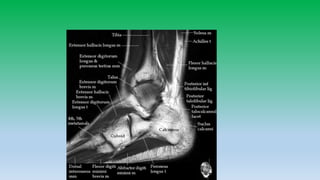

Anterior ankle tendons:

• There are four tendons from medial to lateral –TA, EHL,EDL,PT. These

tendons serves as dorsiflexors of foot and ankle.

• They are seldom affected with tibialis anterior being most commonly

involved.